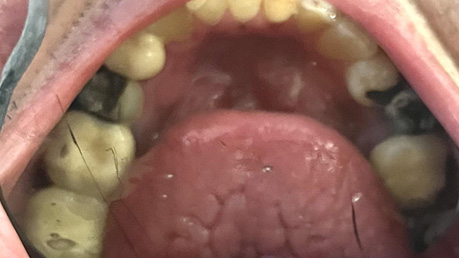

Patient Intraoral Photographs

- Maxilla